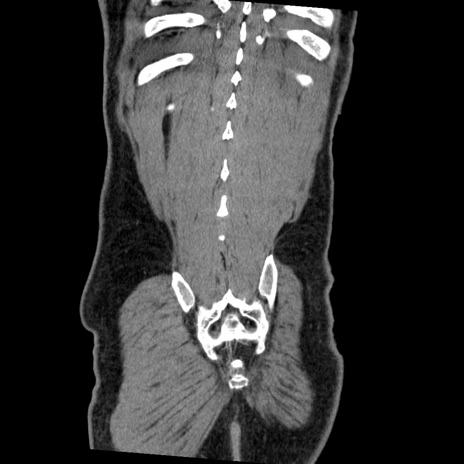

症例22(冠状断像)

【症例】50歳代男性

【主訴】腹痛

【現病歴】AVMからの被殻出血のため回復期リハ病棟入院中。 本日午後3時頃急に下腹部痛が出現した。

【既往歴】AVM、被殻出血、虫垂炎、高血圧

【身体所見】意識晴明、左半身不全麻痺、会話の理解は良好、36.5°C、腹部:膨隆、全体に板状硬、下腹部正中に圧痛点あり、反跳痛-、筋性防御不明、右下腹部にope scar

【データ】WBC 9400、CRP 0.06